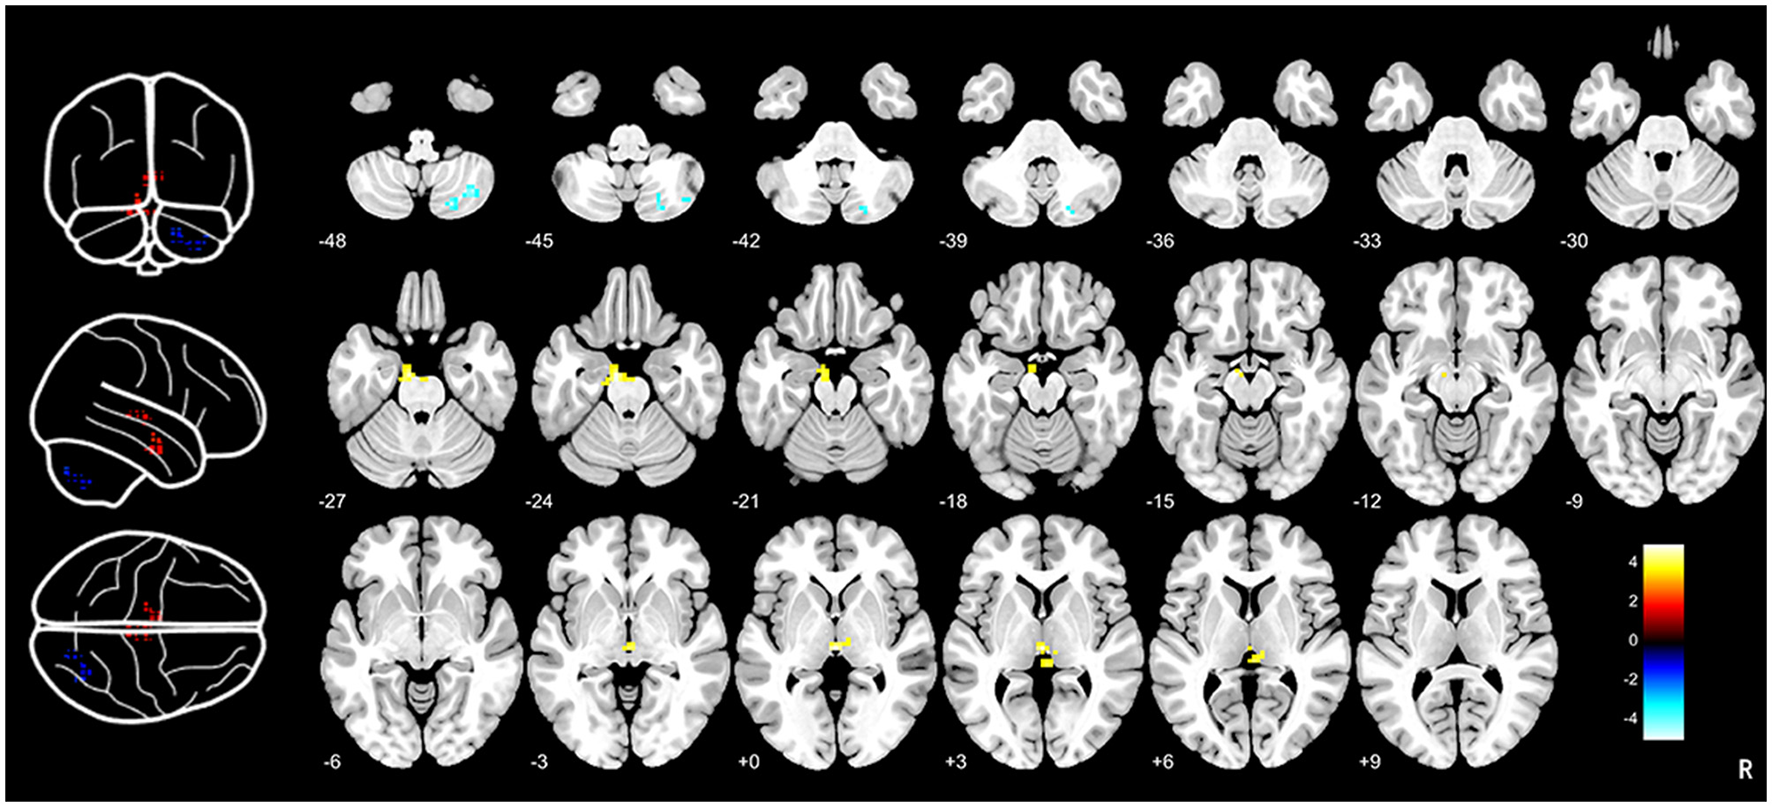

Compared to HCs, CTN patients exhibited distinct patterns of BEN changes in the brain (Table 2, Figure 1). Specifically, increased BEN was observed in the thalamus (voxel p < 0.001, cluster p < 0.05, GRF correction, cluster size > 32 voxels) and pons (voxel p < 0.001, cluster p < 0.05, GRF correction, cluster size > 32 voxels), suggesting enhanced neural activity and complexity in these areas. Conversely, decreased BEN was found in the inferior semilunar lobule (voxel p < 0.001, cluster p < 0.05, GRF correction, cluster size > 32 voxels), indicating disrupted neural processing and complexity in this region. Further analyses revealed a low positive correlation between the average BEN values of the thalamus and neuropsychological assessments (SAS and SDS), regressing out the covariates of age, sex, education, and head motion (Figure 2, Table 3).

Figure 1

Brain entropy analysis between CTN patients and HCs. Brain entropy map showed that significant differences in thalamus, pons and inferior semilunar lobule between CTN patients and HCs. Increased BEN was observed in the thalamus (voxel p < 0.001, cluster p < 0.05, GRF correction, cluster size > 32 voxels) and pons (voxel p < 0.001, cluster p < 0.05, GRF correction, cluster size > 32 voxels) and decreased BEN was found in the inferior semilunar lobule (voxel p < 0.001, cluster p < 0.05, GRF correction, cluster size > 32 voxels). CTN, classical trigeminal neuralgia; HCs, healthy controls.